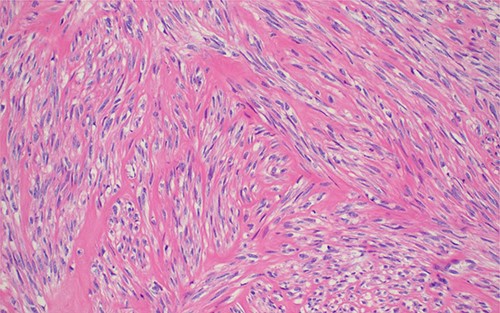

Histopathology of the lesion demonstrating monotonous population of spindle shaped cells in intersecting fascicles without cytological atypia; H&E stained sections 100× original magnification.

The definitive diagnosis is achieved by histology. Microscopically, leiomyoma consists of monomorphic spindle cells with blunt-ended nuclei, arranged in interlacing fascicles, without atypia, mitosis or necrosis [4, 6, 7].